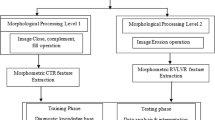

Nowadays, prediction of abnormality plays a vital role in healthcare applications for deciding the treatment and guiding for proper treatment on time. The amniotic fluid is the water of the womb, and it is a strong indicator of congenital fetal anomaly. The automatic calculation of amniotic fluid index (AFI) and shape features of varying gestational periods will be useful to predict the perinatal outcome of high risk in maternity patients. Some perinatal outcomes are expected fetal weight, head circumferences and need of new-born ICU which decide the mode of delivery. These perinatal outcomes will be helpful in increasing the live birth and reducing the risk of premature delivery. The aim of this work is to identify the abnormal AFI of expectant mothers to alert the clinicians. Computer-aided diagnosis supports the clinicians in decision-making process. In the proposed work, using the training set of ultrasound images, the shape templates are developed by using deformable methods. Contour points in the edges will be helpful to find the AFI. After that, features are extracted and fuzzy logic algorithm is used to classify the given image into one of the four categories such as oligohydramnios, borderline, normal and hydramnios state for expectant mothers and their impact on fetal growth. The outcome of the proposed approach is measured in two different ways. The first outcome is that calculated AFI will be compared with the value calculated by the radiologist/clinicians, and the second outcome is that along with AFI, shape feature with contour points and gestational age are used for making decision/classification such as normal, borderline, oligohydramnios and hydramnios, and the classified results will also be compared with the expert’s opinion. The outcomes are represented quantitatively. The results proved that AFI calculated by the proposed work was matching 94% with the expert opinion and classification of test image into any one of the categories such as normal, borderline, oligohydramnios and hydramnios fetched average accuracy of prediction up to 92.5%.